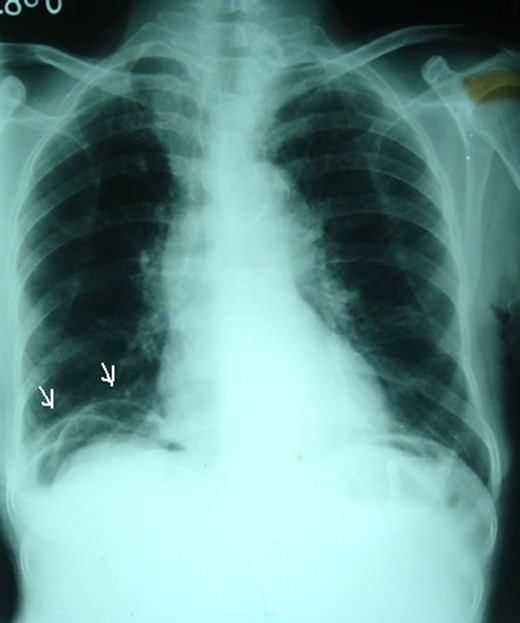

Plain supine abdominal radiograph showed features of small bowel obstruction. However, a plain chest radiograph taken in erect position showed radiolucent shadow under the right dome of the diaphragm, first simulating pneumoperitoneum (Fig. 1). The impression of free gas under the diaphragm was very much supported by the clinical finding of obliterated liver dullness. However, on careful examination of the radiograph, few semilunar radio-opaque linings could be seen, which could be walls of bowel loops (Fig. 2). She was diagnosed as acute intestinal obstruction, probably Chilaiditi's syndrome: we thought of obstruction due to herniation into the hepatodiaphragmatic space.

A plain erect chest radiograph showing appearance of radiolucency under the right hemidiaphragm (arrows).